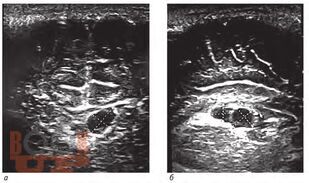

Внутрижелудочковые кровоизлияния у недоношенных новорожденных

В учебном пособии рассматривается проблема персонализации медицинской помощи недоношенным новорожденным с внутрижелудочковыми кровоизлияниями.

Учебное пособие предназначено для неврологов, неонатологов, нейрохирургов, врачей ультразвуковой диагностики и врачей других специальностей, участвующих в оказании медицинской помощи новорожденным с внутрижелудочковыми кровоизлияниями.